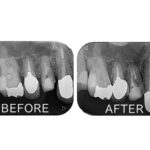

こちらが初診時のレントゲンとお口の写真になります。

右上の1番目の歯がすでになく、右上の2番目と左上の1番目の歯でブリッジが入っている状態です。ブリッジは、他の歯の色に比べ、白く不自然な色となっています。さらに、左上1番目の歯茎が腫れてしまっているのが良くわかります。

患者様のお口の中を診察させていただき、レントゲン写真を撮影して、現在の歯の状態について詳しく調べました。調べた結果、ブリッジを支えている左上1番目の歯の根にヒビが入っている状態(歯根破折)でした。歯根破折が生じた歯は、ヒビに沿って細菌が感染し、周りの骨が溶かされ、歯茎が赤く腫れ上がり炎症を起こす原因となるため、抜歯が必要となります。